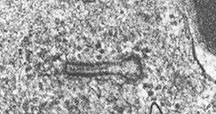

- Birbeck Granules: Electron Microscopy demonstrates granules that often take the form of a tennis raquet and form from complex invaginations of the cell membrane